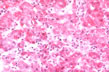

"Multifocal necrosis"

Fig 45 - MULTIFOCAL NECROSIS: PaMultiple focal areas of liver cell damage that can be very serious. In this slide the damaged cells are the light ones which have lost their glycogen content represented by the red granular material that stains red with the PAS reaction.